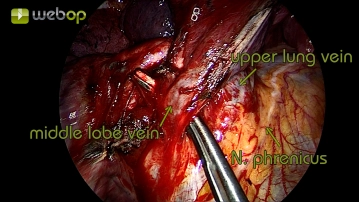

Präparation der Mittellappenvene

Toneinstellungen Nach Darstellung der Pulmonalarterie und Resektion der Parenchymbrücken erfolgt jetzt die Präparation am Lungenhilus. Die obere Lungenvene zeigt sich im Situs bereits ohne weitere Präparation. Für gewöhnlich drainiert die Mittellappenvene in die obere Lungenvene und kann dort eindeutig identifziert werden. Der Verschluss erfolgt hier mittels TitanClips.

Durch Anheben des Mittellappens kann nach Dissektion der Mittellappenvene mit Blickrichtung vom Hil